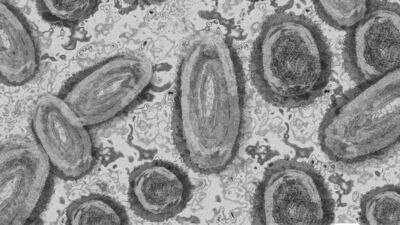

Gana Sağlık Servisi (GHS), ülkenin 10 vilayetinde 34 yeni M-çiçeği (mpox) vakasının tespit edildiğini duyurdu ve toplam vaka sayısının 79’a ulaştığını bildirdi. Açıklamada, virüs nedeniyle 4 kişinin hastanede tedavi gördüğü, temaslı takibinin devam ettiği ve ülke genelinde gözetim çalışmalarının yoğunlaştırıldığı belirtildi.